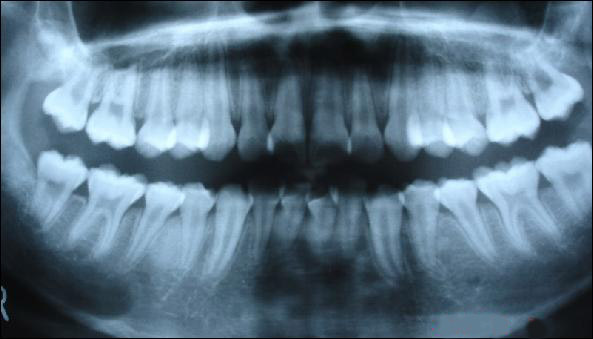

上圖為健康人的全口曲面斷層片,俗稱骷髏片

從上圖可以看出,牙槽骨被吸收,牙齦萎縮,牙縫變大